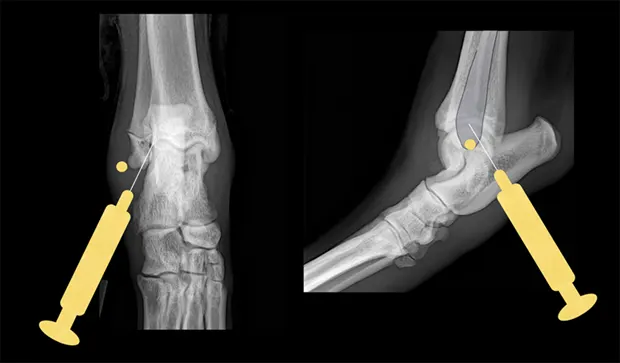

Tarsus

Place the patient in lateral recumbency with the affected limb on top. The lateral aspect of the joint usually provides the best yield of fluid because this area has the least villous synovium. In large-breed dogs, insert a 22-gauge, 1-inch needle in the caudodistal aspect of the distal fibula (lateral malleolus) at a 30°–45° angle from caudodistal to cranioproximal and in a distolateral-to-proximomedial direction. Another option is the dorsal joint pouch approach: place the needle between the tibia and talus to the medial or lateral side of the saphenous vein and extensor tendons.

Lateral and craniocaudal views of hock. Insert the needle just distal to the lateral malleolus at a 30°–45° angle in a craniomedial direction.